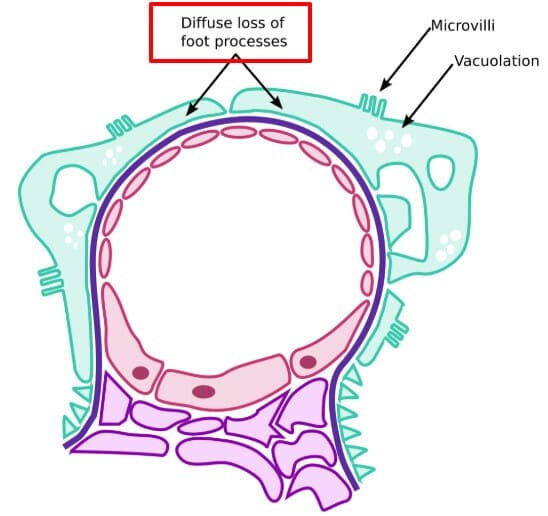

Minimal Change Disease (MCD)

Minimal Change Disease (최소변화병증)

T세포 이상으로 인해 podocyte의 구조적 손상이 발생하며, 단백질 여과 장애가 생깁니다.

[특징]

소아에서 가장 흔한 신증후군 원인입니다.

광학현미경에서는 정상으로 보이지만, 전자현미경에서 podocyte의 foot process 소실/ 광범위한 유합이 관찰됩니다.

[치료]